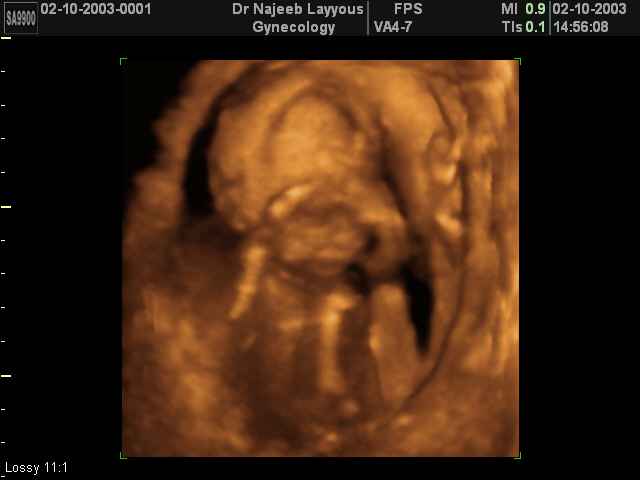

3D second trimestre échographie Photos de numérisation - deuxième partie de la grossesse | Dr N Layyous

3D second trimestre échographie Photos de numérisation - deuxième partie de la grossesse